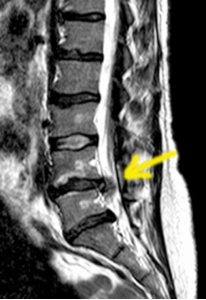

Die nebenstehende Abbildung zeigt das Bild einer Lendenwirbelsäule (LWS), aufgenommen mit dem Diagnoseverfahren der Magnetresonanz-Tomografie (MRT) Der gelbe Pfeil weist auf einen Bandscheibenvorfall im Segment L4/5 hin (dunkler Fleck).

An der LWS haben wir fünf Wirbel und auch fünf Bandscheiben. Ca. 95 % aller Bandscheibenvorfälle treten an der Lendenwirbelsäule auf. Die meisten Bandscheibenvorfälle finden wir an den untersten zwei Bandscheiben (L4/5 und L5/S1)